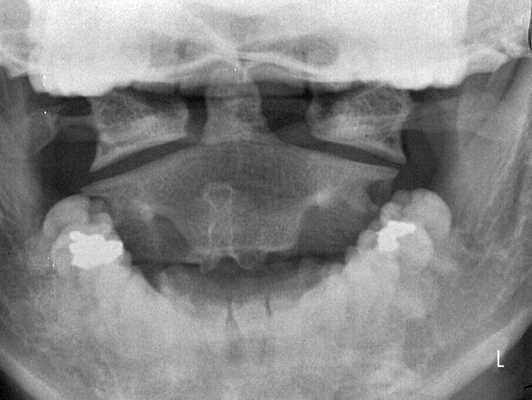

Рентгенологическое исследование является основным методом диагностики. Шейный отдел позвоночника исследуется в пяти проекциях:

- переднезадняя проекция;

- боковая;

- снимки в боковой проекции со сгибанием и разгибанием головы;

- прямой снимок через открытый рот. [3]

Этот стандарт исследования минимизирует возможность ошибок диагностики, так как подвывих иногда выявляется только на функциональных снимках. Исследование шейного отдела позвоночника в двух или трех стандартных проекциях не дает достаточной информации, чтобы диагностировать подвывих атланта, который часто остается нераспознанным. [4]

Для исследования грудного и поясничного отдела используются переднезадняя и боковая проекции, включая снимок со сгибанием и разгибанием. В ряде случаев дополнительно проводится МРТ или КТ позвоночника, при осложнениях — электромиография и ультразвуковое исследование сосудов головного мозга. [12]